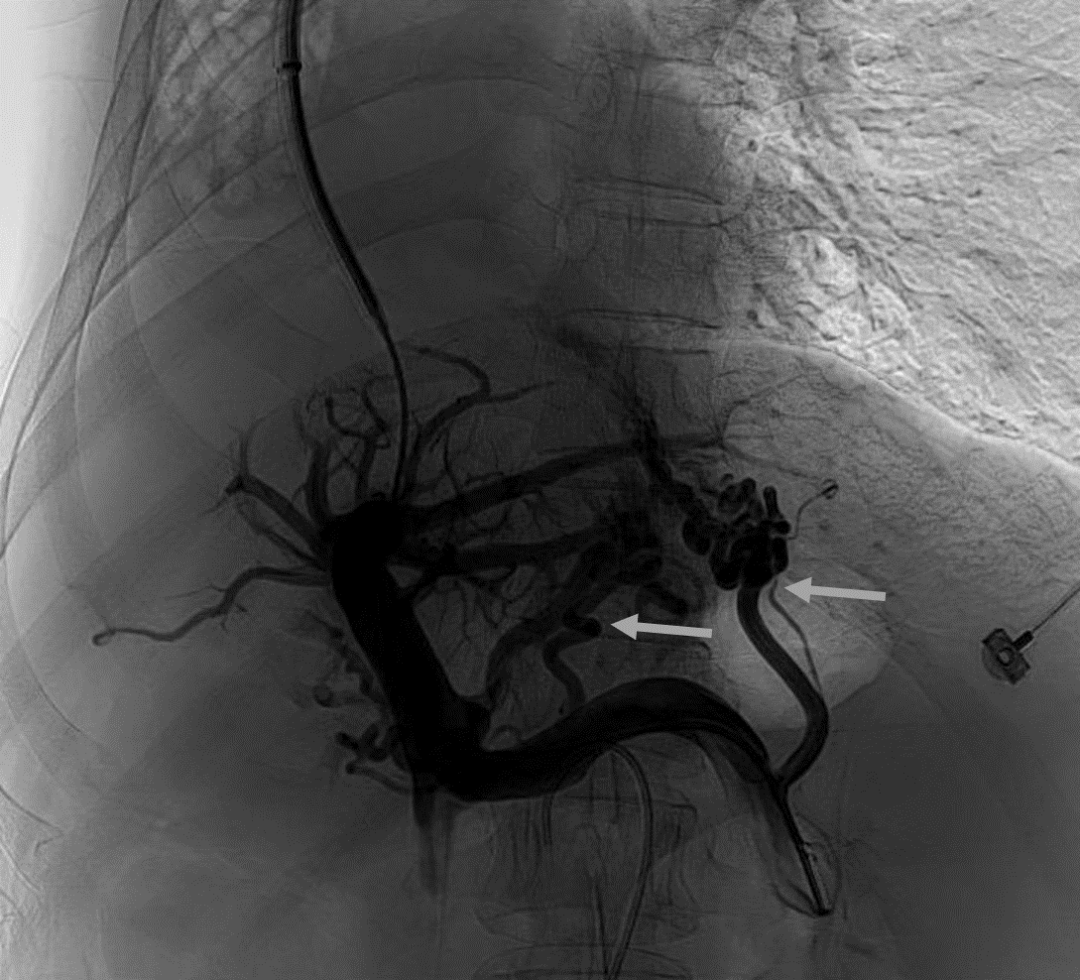

韓國宏教授介紹,TIPS手術是通過在肝靜脈與門靜脈之間的肝實質內建立分流通道,通過降低門靜脈壓力來預防和治療因門靜脈高壓引起的食管胃底曲張靜脈破裂出血或頑固性腹水。該手術不用開刀、創(chuàng)傷小、操作過程復雜、技術難度大、安全風險高,是目前外周血管介入中難度最大的手術之一。再加上人群中右位心發(fā)病率極低(約萬分之一),經(jīng)查閱文獻,在國內外尚未有類似病例報道,無經(jīng)驗參考。在右位心基礎上行TIPS術,無疑是難上加難。我們反復研究患者肝臟及心血管的特殊情況,詳細討論了手術方案,決定放棄常規(guī)的肝靜脈穿刺,另辟蹊徑,選擇高難度高風險的肝后段下腔靜脈穿刺門靜脈左支,憑借多年的經(jīng)驗和嫻熟的技術最終成功的在下腔靜脈與門靜脈之間放置了TIPS專用支架,術后門靜脈壓力梯度從術前的19mmHg降至3mmHg,曲張靜脈消失,解決了困擾曹女士多年上消化道出血的困擾。患者術后第二天即可正常下床活動。